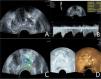

A 76-year-old patient had a total PSA of 14.3 ng/mL. Multiparameter US started with conventional transrectal ultrasound, and the lesion was a hypoechoic nodule at the junction of the inner and outer glands in the prostate’s left lobe (A, arrow). The lesion appeared on CDU with rich blood flow in the arterial spectrum (B, arrow). The operator used the endocavitary transducer to alternate between compressing and decompressing the lesion, which appeared mostly blue on TRTE (C, arrow). A hypoechoic nodule appeared on CEUS as a hypervascular nodule with a “fast in, fast out” enhancement pattern (D, arrow). Histopathology showed that the prostate lesions were clinically significant and Gleason 4 + 3 PCa.

Grayscale ultrasound examinationTransrectal GSU was routinely performed using a GE Voluson E10 ultrasound system (GE Healthcare, Milwaukee, WI, USA) with a 3.5‒8 MHz rectal convex array probe (RIC 5–9-D). Before the examination, the patients were asked to empty their bowels and were positioned in a left lateral decubitus position. Then, a sonographer inserted the probe into the patient's rectum and preliminarily evaluated the shape, size, internal parenchymal echo, and integrity of the capsule of the prostate through multiple views, such as longitudinal and transverse sections. The criteria for GSU were as follows: a hypoechoic lesion in the prostate parenchyma was suspiciously positive, and isoechoic or hyperechoic lesions were considered negative (Fig. 1A; Fig. 2A).10

The CDU/PDU examination of suspicious areas followed the grayscale ultrasound examination described above. The richness of blood flow in the parenchyma and the presence or absence of abnormal blood flow branches were observed. The criteria for Doppler ultrasonography were as follows: areas with rich blood flow or multiple abnormal blood flow branches compared with the surrounding normal prostate tissue were suspiciously positive, and areas with consistent blood flow or reduced blood flow compared to the surrounding normal tissue were considered negative (Fig. 1B; Fig. 2B).14

Transrectal real-time tissue elastographyBy engaging the dual display function for grayscale images and elastic images at the same time, TRTE examination on the hypoechoic area from GSU and the area with abnormally increased blood flow from Doppler ultrasound was performed. The suspicious area was placed in the sampling frame, and the probe was used to regularly and gently press the gland 1‒2 times/second with a pressure index of approximately 4. The optimal force and frequency of the manual compressions of the prostate were monitored by the visual color bar and waveform indicators. The images were frozen and stored after 3‒5 stable waveforms appeared in the elastogram. Different colors on the TRTE elastogram marked different densities of prostate tissue, with blue indicating hard tissues and red indicating soft tissues. PCa is stiffer than normal prostate tissue and often appears blue on TRTE images due to increased cell density, microvascularization, and collagen deposition from the matrix reaction. The criteria for TRTE were as follows: a blue area > 50 % in the nodule was suspiciously positive, and an area ≤ 50 % was considered negative (Fig. 1C; Fig. 2C).15

Contrast-enhanced ultrasound examinationThe microbubble suspension-based contrast agent SonoVue (Bracco Imaging SpA, Milano, Italy, 2.4 mL) was fully mixed with 5 mL of 0.9 % NaCl solution and was administered intravenously. The examination was started after the injection of the microbubble suspension and performed with a mechanical index of 0.2. Data such as contrast enhancement time, enhancement intensity, and contrast agent disappearance time in the suspiciously marked lesions of the prostate were recorded synchronously. After the contrast agent completely dissipated, the sonographer repeated the same examination again. The criteria for CEUS were as follows: early hyper enhancing areas in the prostate were suspiciously positive, and areas of simultaneous or late, isoenhancing or hypo-enhancing areas were considered negative (Fig. 1D; Fig. 2D).16 The results of all the above examinations were judged independently by two sonographers. Both sonographers are professors of ultrasonic diagnostics. The data used for the later logistic regression analysis were the results from only a senior experienced sonographer. The data for the repeatability test were additionally obtained from another sonographer with similar clinical experience who examined a random sample of patients compared to the previous sonographer.